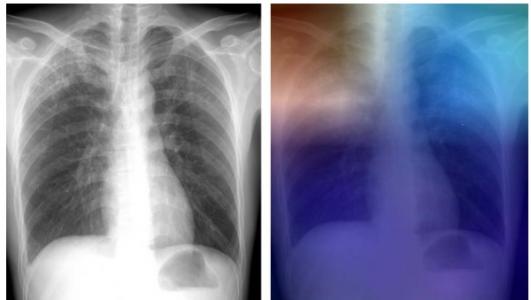

La tuberculose est l'une des 10 principales causes de décès dans le monde (OMS). En 2016, la maladie a touché plus de 10 millions de personnes entraînant 1,8 million de décès. La tuberculose peut être identifiée via l'imagerie thoracique, mais les zones endémiques ne disposent généralement pas de l'expertise radiologique requise pour dépister et diagnostiquer la maladie. L'intelligence artificielle ici basée sur ce que les chercheurs nomment « l'apprentissage approfondi » peut être un recours précieux pour « remplacer » l'expertise radiologique qui fait défaut dans certaines zones endémiques. Le Dr Paras Lakhani, de l'Hôpital universitaire Thomas Jefferson (Philadelphie), co-auteur de l'étude explique : « Une solution d'intelligence artificielle qui pourrait interpréter des radiographies et détecter la présence de la tuberculose pourrait accroître la portée de l'identification et du traitement précoce dans les pays en développement ». C'est tout le développement effectué par son équipe, celui d'un type d'intelligence artificielle qui permet aux ordinateurs de compléter les tâches en fonction des relations des données existantes. Un réseau inspiré de la structure du cerveau exploite plusieurs couches de données et de motifs « cachés » pour mieux interpréter les images. Un modèle qui peut atteindre 99% de précision : un modèle réalisé à partir de 1.007 images de patients avec et sans tuberculose active apportant de multiples jeux de données de radiographie thoracique a permis aux chercheurs de développer plusieurs modèles d'apprentissage approfondis qui testés sur 150 cas ne sont en désaccord avec le diagnostic radiologique humain que dans 13 cas seulement. Avec la participation (réduite ou à distance) d'un expert humain, la précision nette du modèle atteint près de 99%. L'exemple est donné ici avec l'image couleur ci-contre : les zones rouges et bleu clair dans les lobes supérieurs représentent les zones activées par le réseau neuronal profond de « l'intelligence artificielle ». Le réseau se concentre ainsi sur des parties de l'image où la maladie est présente (les deux lobes supérieurs). L'équipe travaille toujours à améliorer encore ses modèles pour pouvoir rapidement pouvoir les mettre en application dans un environnement réel : leur solution d'intelligence artificielle utilisant l'imagerie thoracique pourrait prochainement jouer un rôle important dans la lutte contre la tuberculose.

Avril, 2017 Deep Learning at Chest Radiography: Automated Classification of Pulmonary Tuberculosis by Using Convolutional Neural Networks (Visuel@Radiological Society of North America)